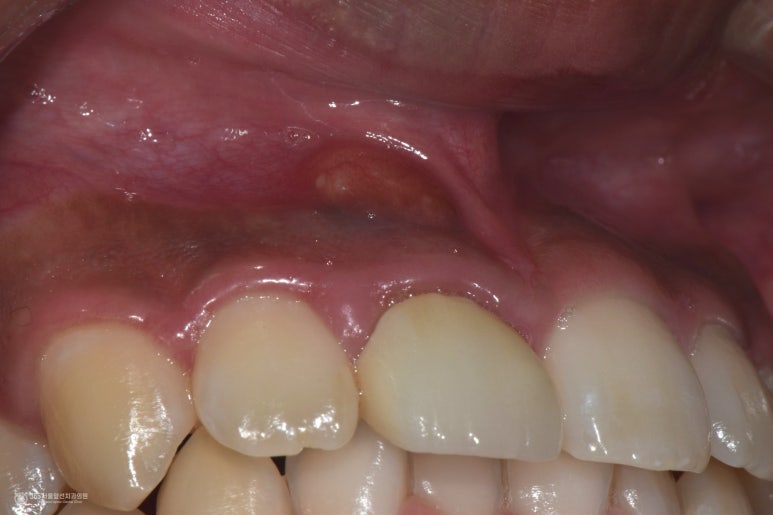

촬영일시 : 2024.09.13 고름이 상당히 커보입니다. 즉, 오랫동안 염증이 지속되어 치아 뿌리 끝에 커다란 고름주머니를 형성시킨 것으로 유추되는데요.